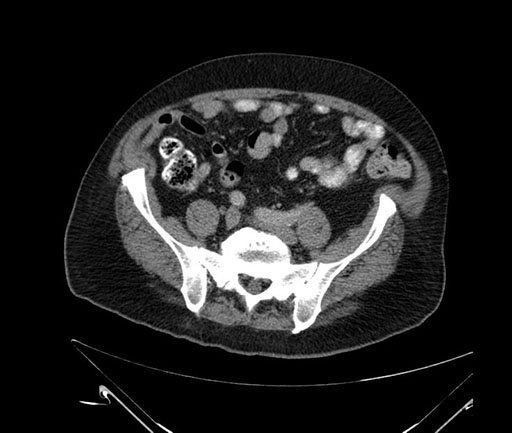

Whipple (pancreaticoduodenectomy) [case 7]

Imaging Analysis

Look through the patient's CT scan to identify any areas of concern for the necessary procedure.

Based on your CT findings, which issue(s) would give reason for "planned slowing down moment(s)" in this case?

Considering a standard Whipple procedure, what step(s) of the operation would you do differently in this case?